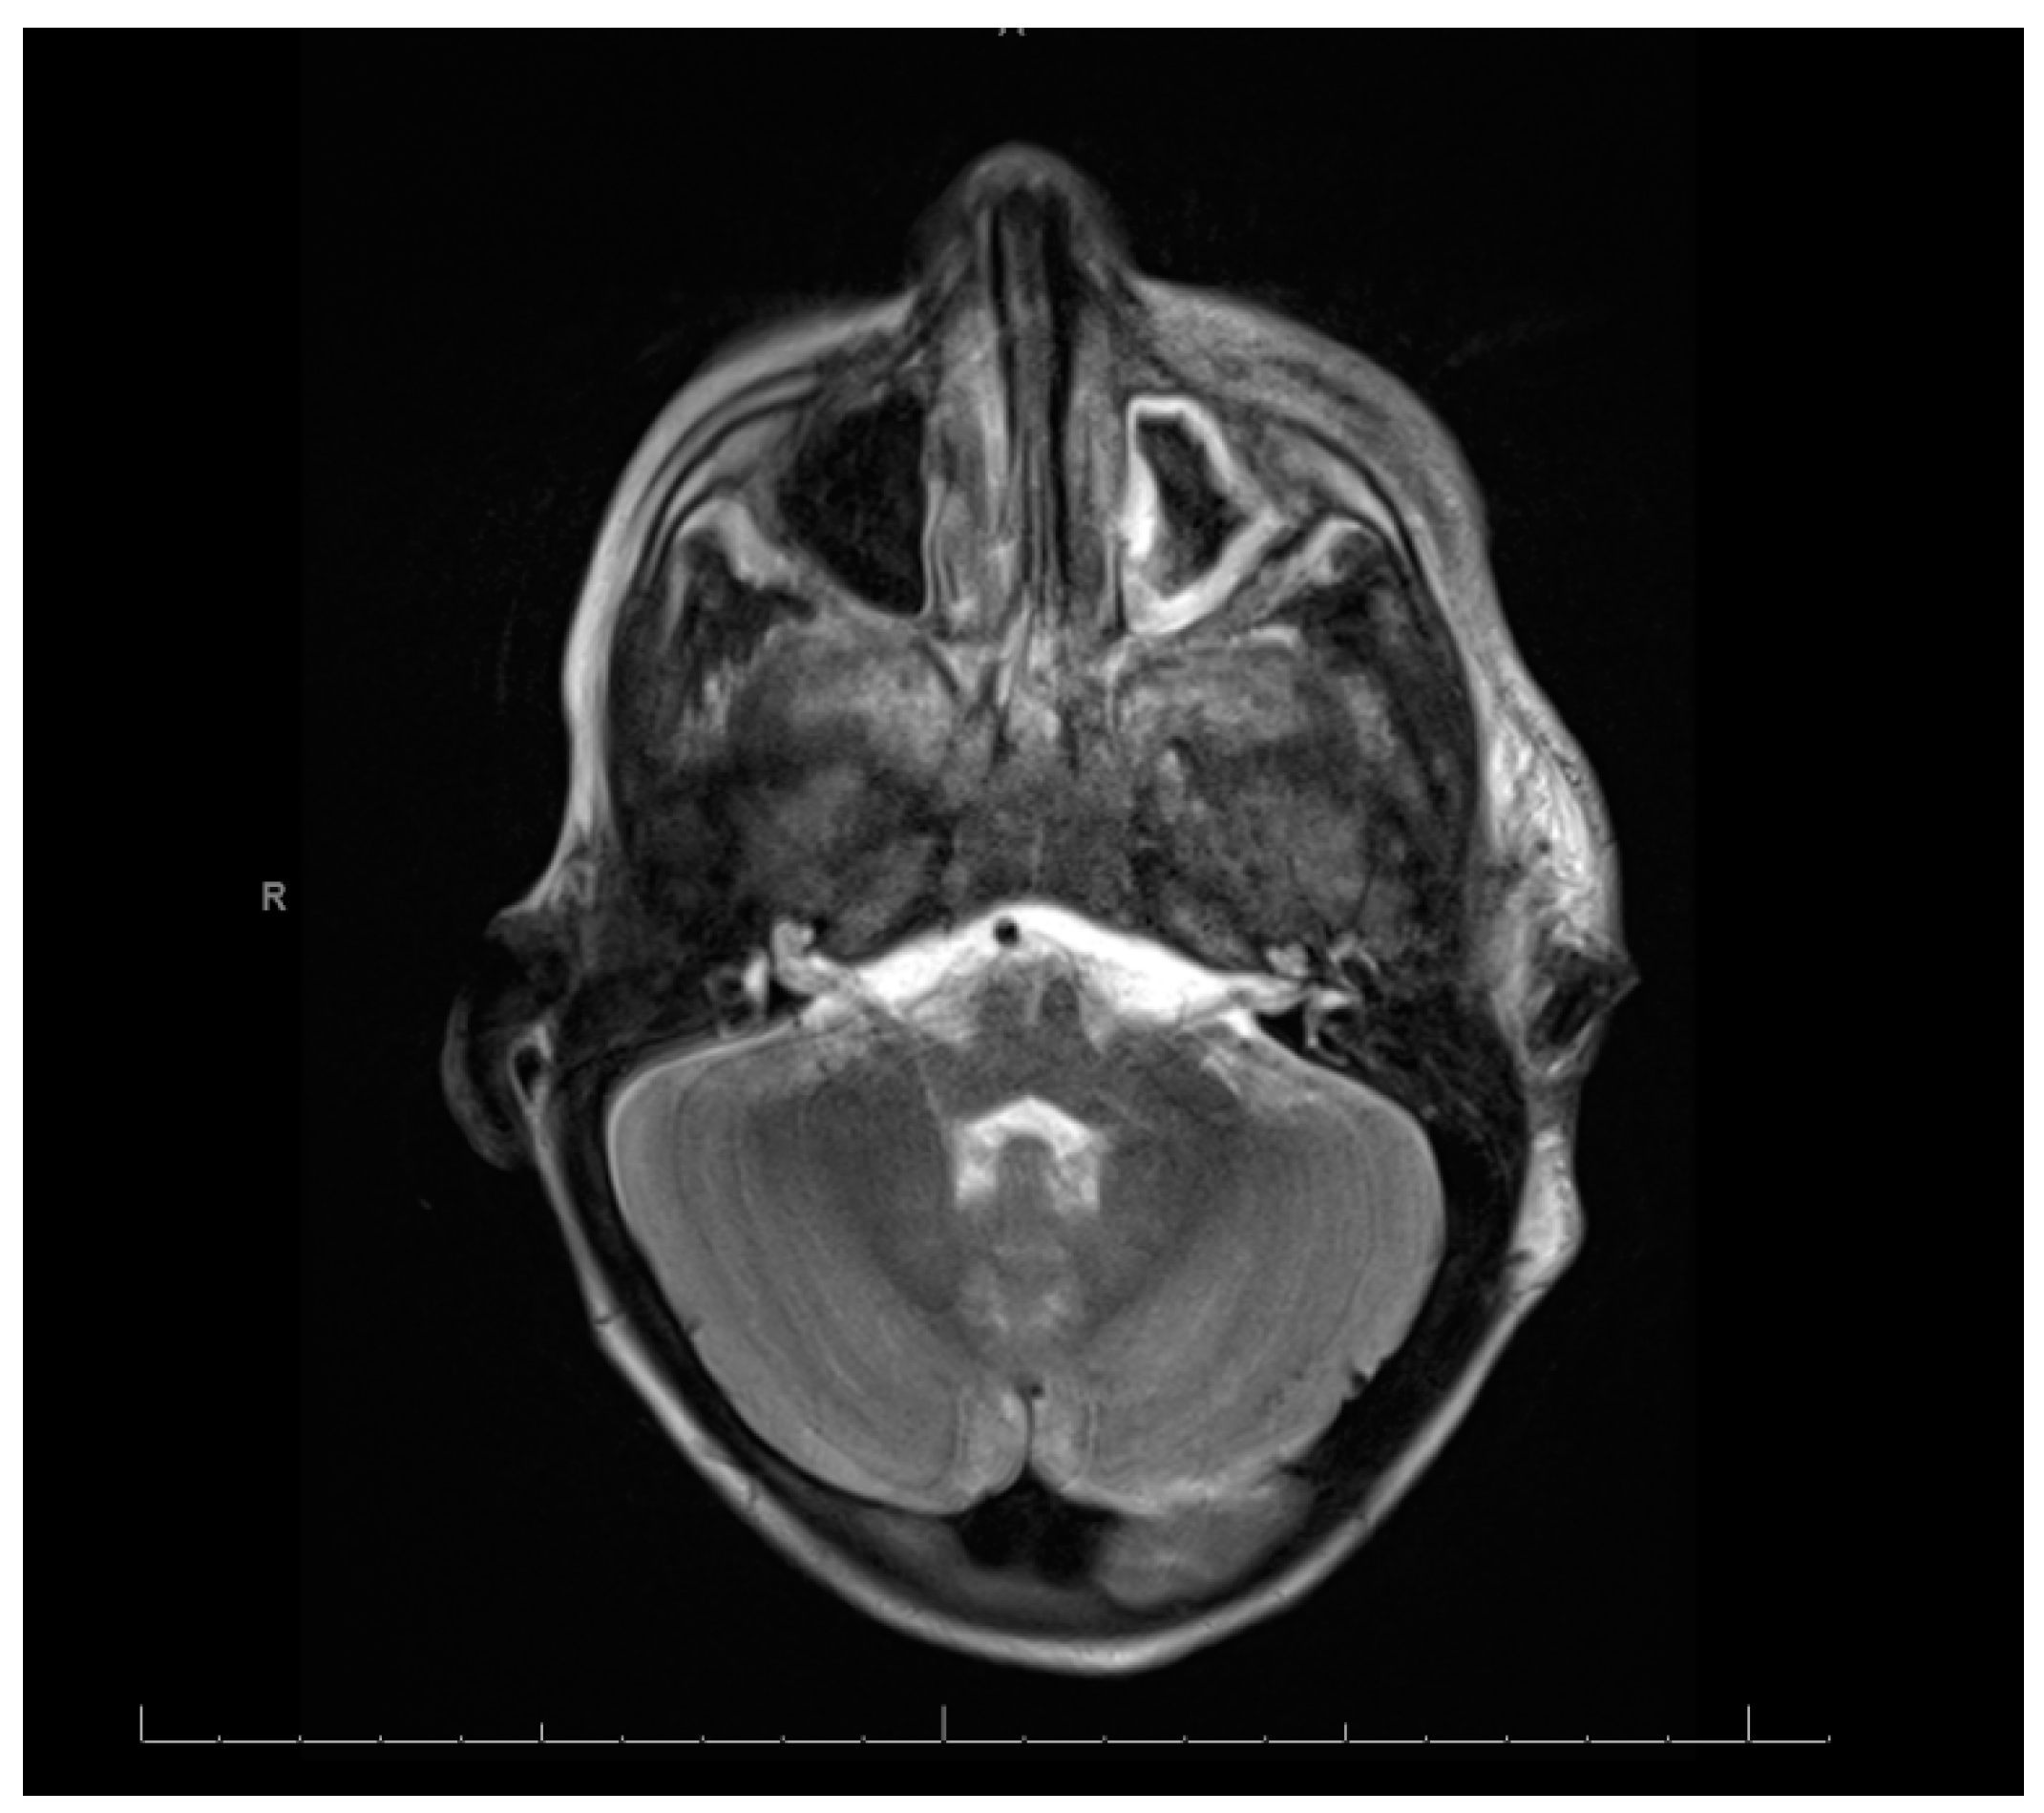

Swabs: A nasopharyngeal swab for a viral multiplex polymerase chain reaction (PCR) was negative. A nasopharyngeal swab for coronavirus disease was negative. A wound swab of the pus aspirate from the oral cavity revealed Gram-negative rods found to be Fusobacterium necrophorum. The identification and susceptibility of causative microorganisms were performed by a VITEK 2 compact system and antibiotic susceptibility testing was interpreted using internationally recognized standards, those established by the Clinical and Laboratory Standards Institute (CLSI) [7]. Cerebrospinal Fluid (CSF): The CSF was clear and colorless. The total WBC was 72 /mm3. The neutrophil content was 94%, the lymphocyte content was 4%, and the monocyte content was 2%. The level of protein in the CSF was high at 0.8 mg/dL, and the glucose value was 2.2 mg/dL. The patient’s gum pus was positive for methicillin-resistant Staphylococcus aureus (MRSA). A blood culture showed Gram-positive cocci in clusters. However, there was no history of any family member with MRSA and the patient was not admitted to the hospital before this admission. Echocardiography: Normal. Electroencephalogram: The electroencephalogram indicated a subclinical seizure. Brain and neck computed tomography (CT) with contrast findings is shown in Figure 1 and Figure 2.

Figure 1 and Figure 2: (A) Loss of corticomedullary differentiation in the right frontal, parietofrontal, and left parietal lobes, indicating a possible microinfarction. (B) Thrombosis in the right internal jugular vein. (C) Left maxillary and ethmoidal sinusitis. The neck CT showed the following: (A) An enlarged heterogenous left parotid gland containing multiple micro-abscesses, with soft tissue swelling and cervical lymphadenopathy, which could represent an infectious/inflammatory process. (B) Right internal jugular vein thrombosis. (C) Multiple bilateral peripheral lung nodules, suggesting that the differential diagnosis could include septic emboli.

Magnetic Resonance Imaging (MRI), Magnetic Resonance Angiography (MRA), and Magnetic Resonance Venography (MRV): Magnetic resonance protocols indicated high T2 signal intensities extensively in the bilateral frontal, parietal, and occipital cortical and subcortical areas, with diffusion restriction. These findings were compatible with acute watershed infarctions with multifocal areas of embolic infarcts, suggestive of severe hypoxic–ischemic encephalopathy. The differential diagnosis included sepsis/septic shock and vasculitis, supporting a stroke workup. The right internal carotid long segment showed severe narrowing/occlusion, and the left internal carotid short segment showed narrowing. The differential diagnosis included vasculitis and sepsis/septic shock with dissection.

The right transverse sinus and internal jugular vein showed thrombosis.

MRA images: The images demonstrate a severe narrowing/occlusion of a long segment of the right internal carotid artery and a short segment of narrowing along the left internal carotid artery. Major intracranial cerebral arteries were patent. MRV images: The images demonstrate an occlusion of the proximal right transverse sinus and narrowing of the right internal jugular vein. The remaining superficial and deep cerebral veins and dural venous sinuses were patent.